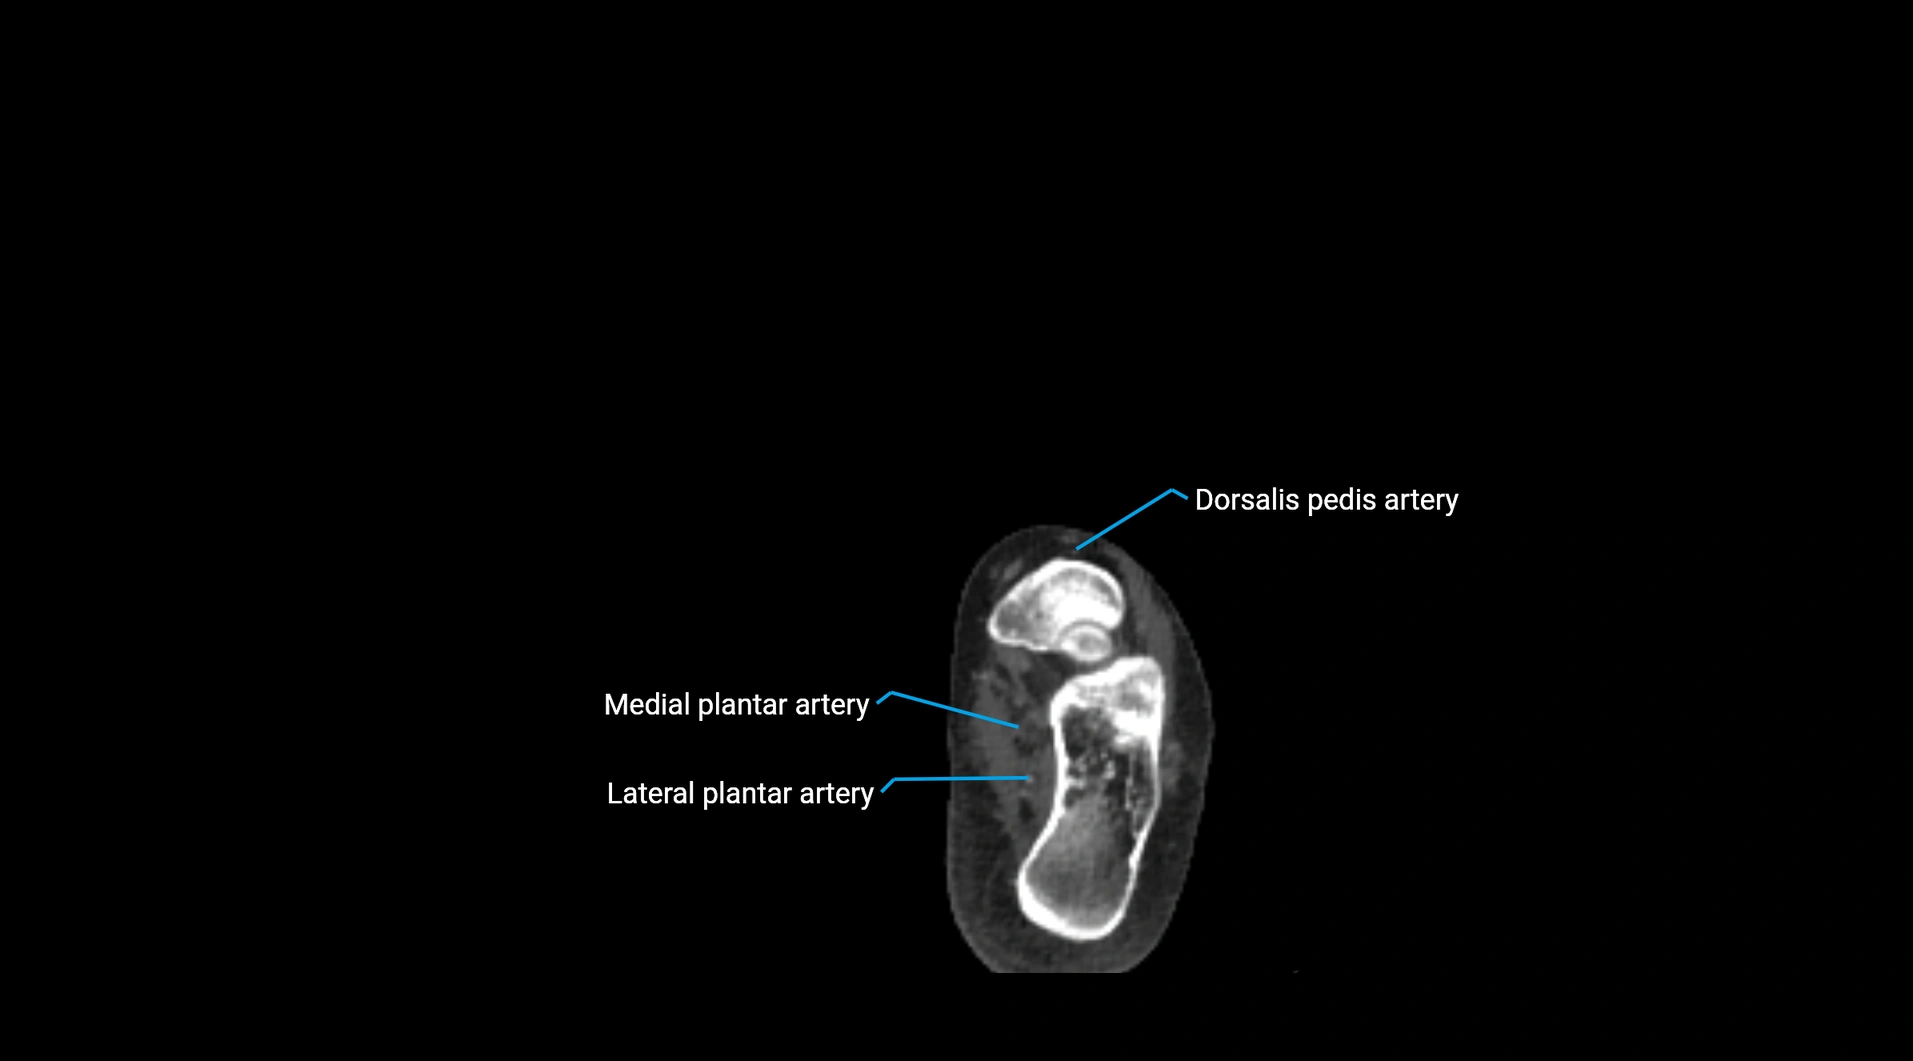

CT images

image